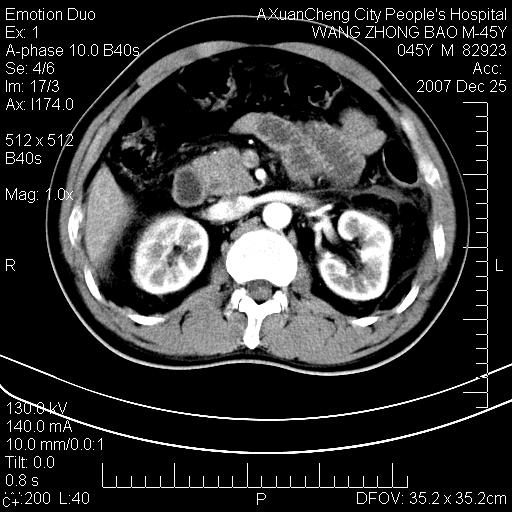

以下是引用qiuleiyu在2007-12-25 18:14:00的发言:[br]胰腺增大,周边渗出改变,肾前筋膜明显增厚,示少量积液.胆囊壁毛糙,周边少许渗出,胆总管壁厚,异常强化,然扩张不明显.结合病程急短;考虑;胆管炎,胆囊炎,胆源性胰腺炎可能大,请结合实验室检查及随访.

以下是引用lisihao在2007-12-25 14:23:00的发言:[br]急性水肿型胰腺炎[br]依据:1、胰腺弥漫性肿大,边缘稍毛糙;[br] 2、双侧肾周筋膜增厚,尤以左侧为甚(重要征象)[br] 3、双侧后胸膜增厚(刺激性炎症);[br] 4、结合病史,查血尿淀粉酶应该可以确诊。